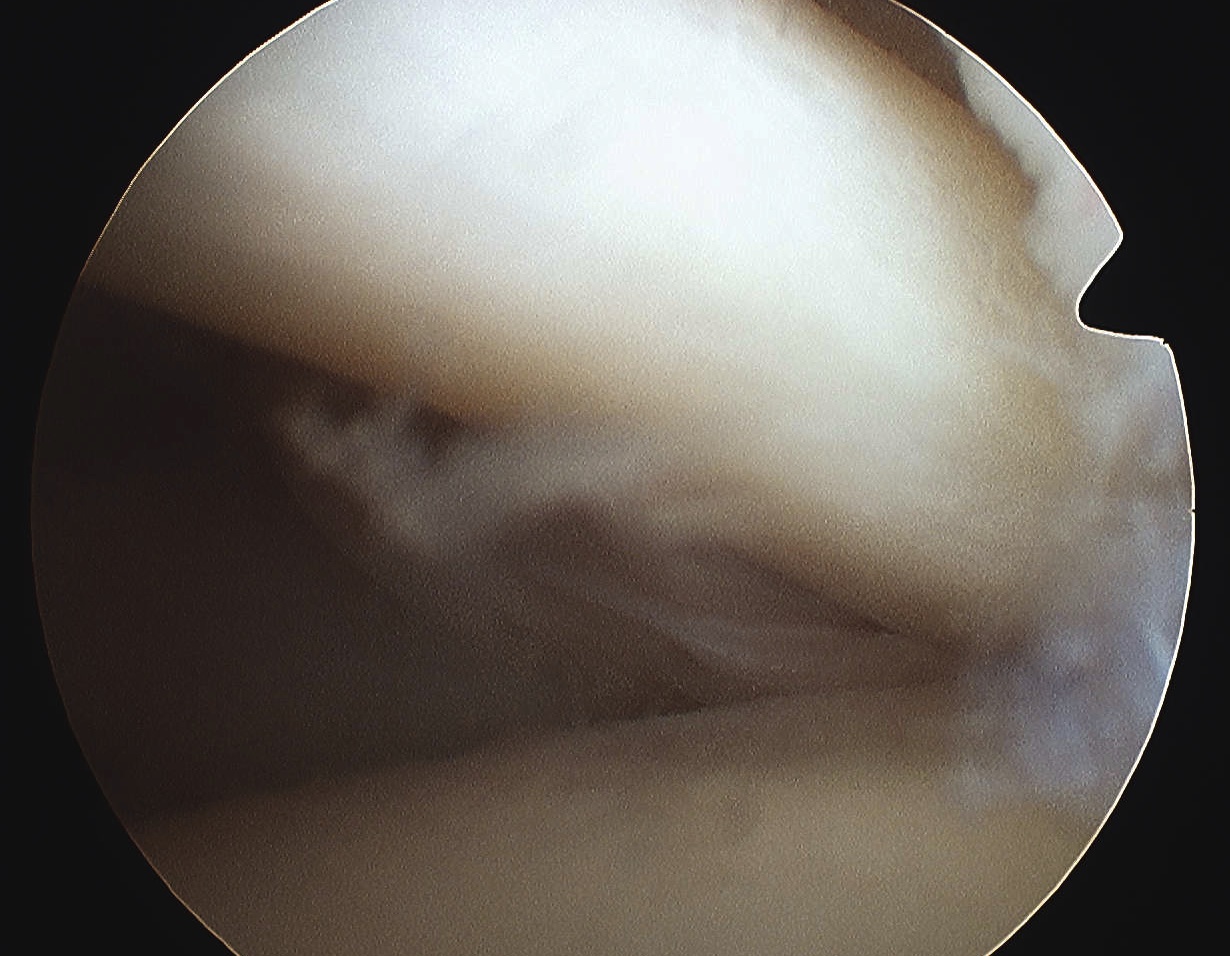

Plantar fascia rupture